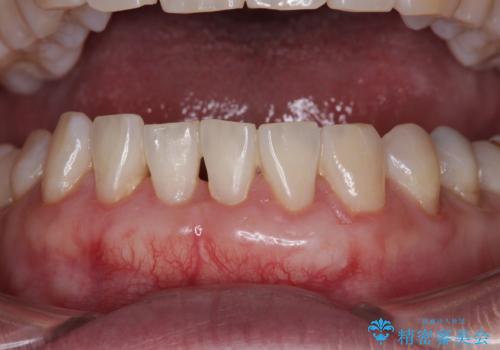

クラウンとなっても出っ歯はさほど改善されず、更には不適なクラウンであったために歯肉が腫れている状態でした。

矯正治療により長年気になっていた出っ歯が改善され、更には歯磨きの度に悩まされていた前歯の出血もなくなり、患者様には大変満足していただきました。